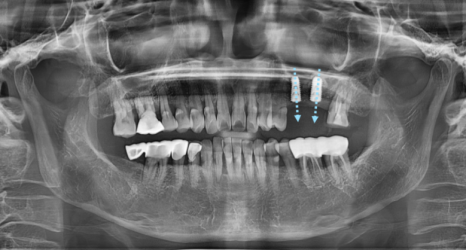

CT와 구강스캐너 데이터를 바탕으로

정확한 각도, 깊이, 위치를 미리 계획하고,

그 계획대로 식립할 수 있도록 디지털 수술 가이드를 제작해 진행합니다.

그렇지만 서울 네비게이션 임플란트 치과에서는

미리 분석하여 계획한대로만 식립하면 되기 때문에

정확도가 향상!

안정적으로 식립할 수 있죠.

수술 후 보철이 올라갈 모습도 예측 가능합니다.

임플란트 사이즈, 두께 , 신경관까지의 위치도 알 수 있습니다.

사전에 턱뼈의 두께, 폭 등 모두 고려하여

각도 및 임플란트 크기

전반적으로 파악

가장 이상적인 수술이 가능한 위치에 식립됩니다.

수술 개수가 많은 경우

더욱 더 요긴하게 활용되고 있습니다.